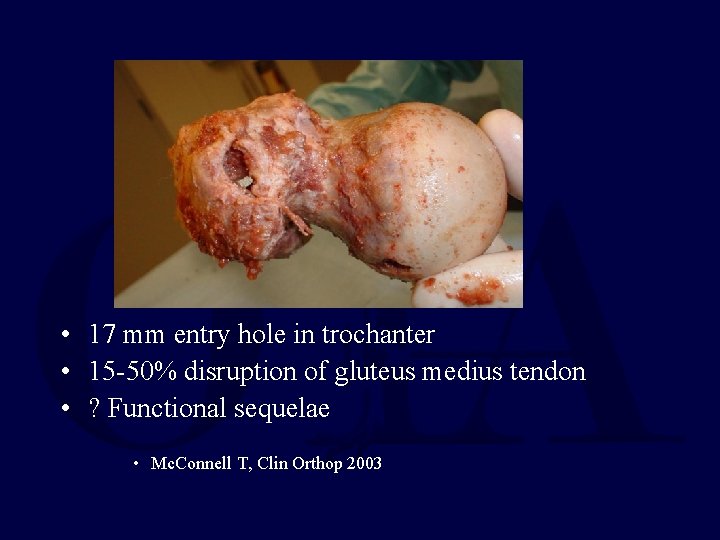

• 17 mm entry hole in trochanter • 15 -50% disruption of gluteus medius tendon • ? Functional sequelae • Mc. Connell T, Clin Orthop 2003